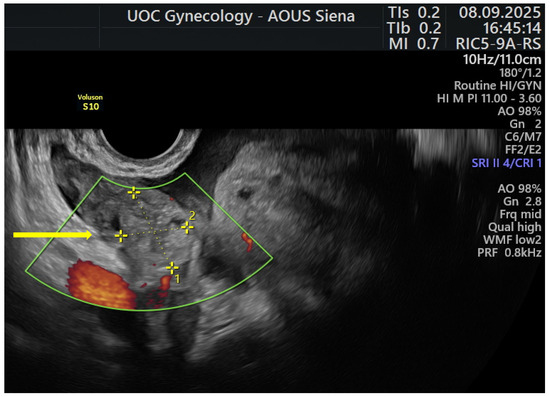

Ectopic Pregnancy with a Normally Located Levonorgestrel-Releasing Intrauterine System in a Woman with Adenomyosis: Case Report and Literature Review

by Francesco Giuseppe Martire, Eugenia Costantini, Errico Zupi and Lucia Lazzeri

J. Clin. Med. 2026, 15(1), 272; https://doi.org/10.3390/jcm15010272 - 29 Dec 2025

Background: Ectopic pregnancy (EP) is a potentially life-threatening condition, often associated with acute abdominal pain and hemoperitoneum. Certain conditions, such as adenomyosis and the use of long-acting reversible contraceptives (LARC), may represent risk factors for the development of ectopic pregnancy. Management is [...] Read more.

Background: Ectopic pregnancy (EP) is a potentially life-threatening condition, often associated with acute abdominal pain and hemoperitoneum. Certain conditions, such as adenomyosis and the use of long-acting reversible contraceptives (LARC), may represent risk factors for the development of ectopic pregnancy. Management is tailored according to hemodynamic stability, reproductive desires, and associated comorbidities. Case Presentation: We report the case of a 39-year-old Caucasian woman with a history of adenomyosis and heavy menstrual bleeding (HMB) treated with a levonorgestrel-releasing intrauterine system (LNG-IUS). She presented to the emergency department with acute abdominal pain, vaginal bleeding, and a rising serum β-human Chorionic Gonadotrophin (β-hCG > 4000 mIU/mL). Transvaginal ultrasound revealed an adnexal mass (24 mm × 19 mm) consistent with a right tubal ectopic pregnancy, associated with hemoperitoneum. The patient, who expressed a desire for definitive sterilization, underwent laparoscopic bilateral salpingectomy. The procedure was uneventful with minimal intraoperative blood loss. Histopathological examination confirmed the diagnosis of right tubal ectopic pregnancy. Literature Review: A case report prompted a focused search of MEDLINE and Scopus (2015–2025) on ectopic pregnancy in users of levonorgestrel-releasing intrauterine systems. Eight eligible case-report studies assessing ectopic pregnancy type and device positioning were ultimately included. Conclusions: This case highlights the importance of early diagnosis of ectopic pregnancy, paying attention to any comorbidities, particularly adenomyosis, the role of minimally invasive surgery, and the possibility of adapting surgical management to the patient’s reproductive wishes. Full article